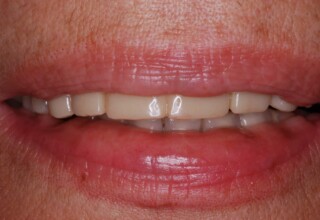

Full mouth prosthetic reconstruction on implants with a different approach on upper and lower jaw

Lower jaw: extractions, direct implant placement and immediate loading (same day) with a transitional bridge.

Upper jaw: Sequential extractions, sequential implant placement and gradual incorporation in the temporary bridge so that the patient was never left without fixed teeth. The aim of the above approach was to have the patient in continuous functional and aesthetic reconstruction, without immediate loading due to anatomical restrictions. Old smiling photos of the patient were used because the natural shape of the teeth was completely lost due to repetitive prosthetic attempts. Tooth relationship and teeth-lip support was transferred to the temporary restorations. Two different transitional bridges were needed to fully estimate phonetics, mastication and esthetics. After the necessary adjustments were finalized, the temporary bridge was used as a guide for the permanent bridges.

Initial